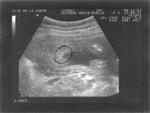

sem 20 écho-4 bébé Catherine C'est une fille, c'est évident! sem 20 écho-5 bébé Catherine Je joue du yokulélé avec papa Je joue du yokulélé